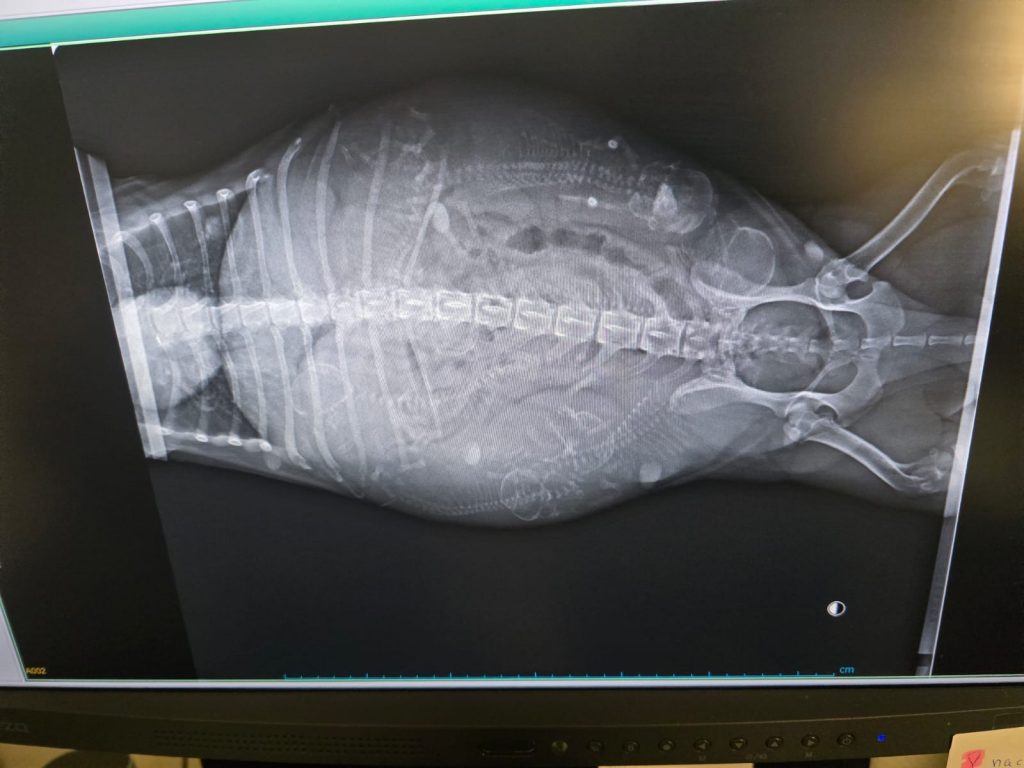

C-Wurf Ultraschall